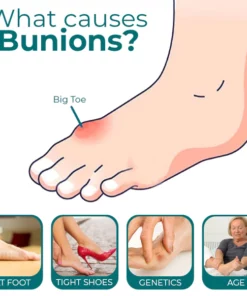

When you have bunions or overlapping toes, long days on your feet can be quite painful. By entering and soothing the underlying tissue to lessen hurting and discomfort, the RASSMAM™ BunionOut Relief Patch can assist in providing that pain relief in a natural way.

- This patch aids in stimulating the lymphatic system, which helps lymph fluids move throughout the body and improve circulation, as well as reducing pain and swelling, accelerating metabolism, and easing stiff joints.

- RASSMAM™ BunionOut Relief Patch are made to straighten your big toe and put it back in its proper place. It not only relieves your toe from the pain, swelling, and pressure brought on by bunions, but it also aids in reducing the bunion so that the joint won’t become misaligned once again. Relieve pain and overlapping toes without surgery.